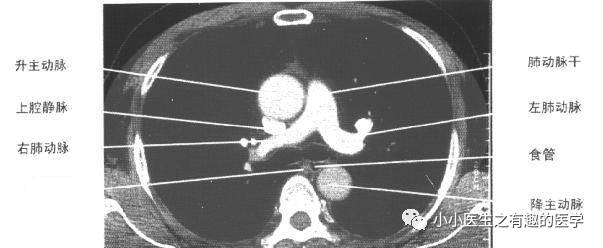

4.一定要知道主动脉弓。因为主动脉弓层面,是肺段划分的常用依据。到了主动脉弓,右肺分为前、尖、后段,左肺分为前、尖后段。这是看肺段的最基本入门知识。

另外,上腔静脉是很基本的血管,要知道。气管很重要,气管的后面,是食道。